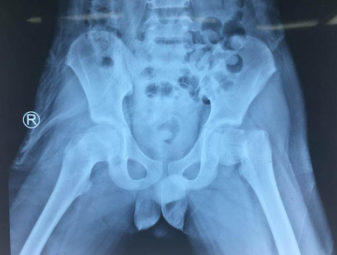

创伤骨科任海东主任接诊后,对小患者进行了仔细的检查,X线片显示:孩子左侧股骨颈骨折,断端错位,周围软组织肿胀。左下肢外旋畸形,较右下肢缩短约2厘米。这种情形,需要手术小心地来进行复位内固定,才能不影响孩子后期的康复与发育。